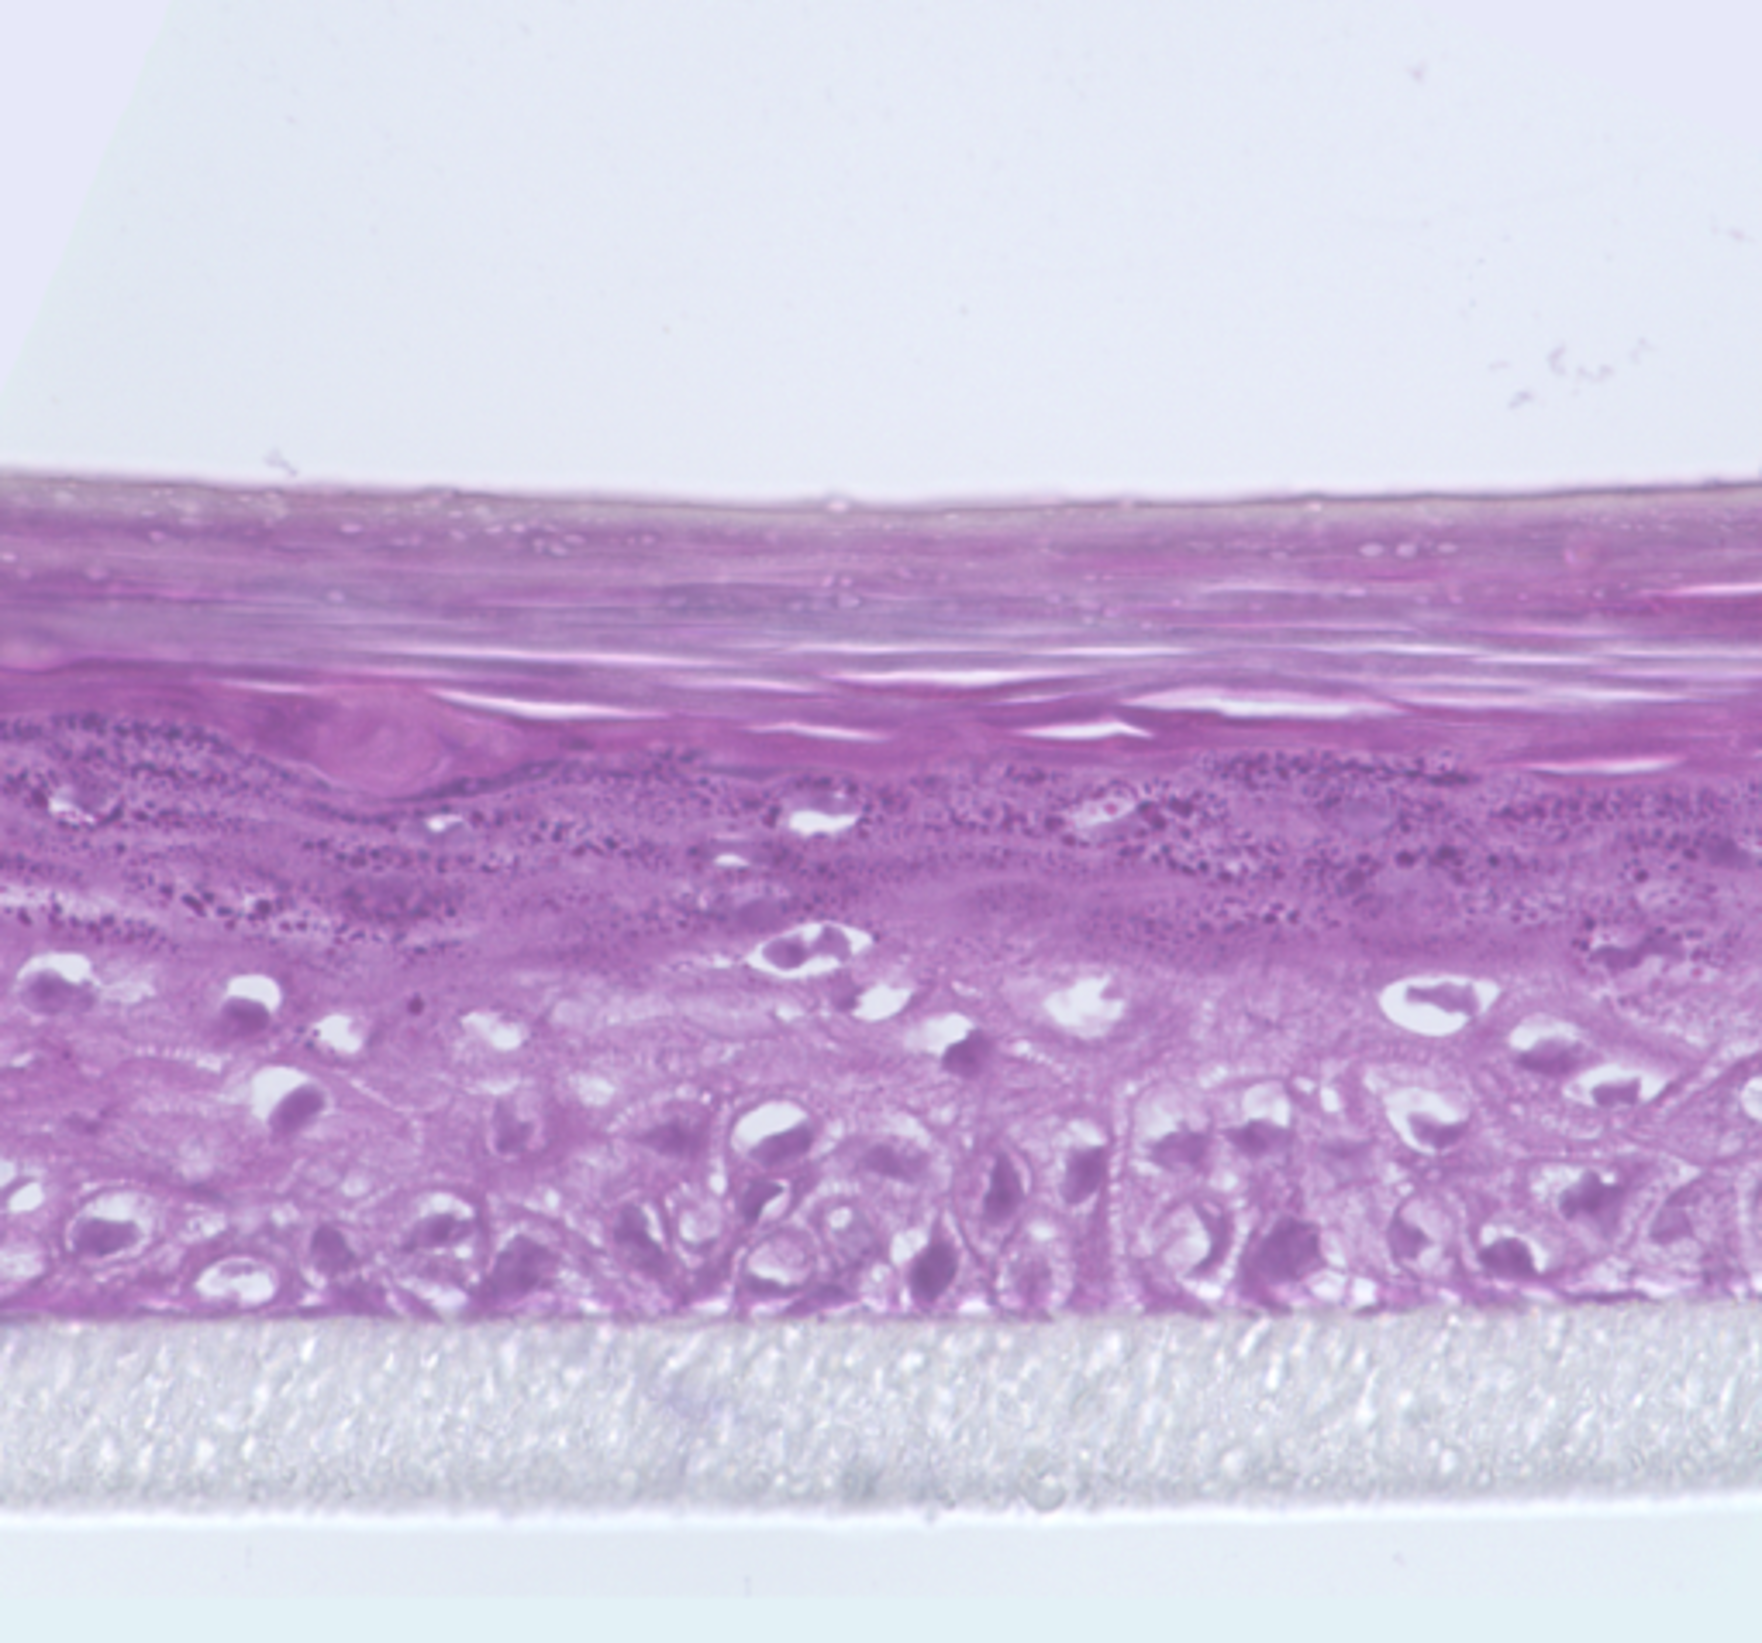

We are interested in developing novel approaches for healing tissue defects (for example, burns and skin wounds) with cultured human skin cells (fibroblasts and keratinocytes) and specially engineered constructs named tissue equivalents composed of cultured cells seeded on scaffolds to mimic the natural structure of tissues. Our lab was established for research in the field of skin biology. Therefore, we have developed several types of skin equivalents which have been implemented in medical practice. Gradually we have come to be interested in the biology and development of skin appendages, that is, skin derivatives developing and functioning as part of it, such as hair follicles and glands. We try to reconstruct hair follicles from adult and pluripotent stem cells in order to understand cell-cell interactions better, especially during hair follicle generation in embryogenesis and also to make progress in the treatment of severe alopecia (balding). Currently, we focus on the generation of fully functional skin equivalents with appendages, including those derived from pluripotent stem cells.

Tissue engineering

We have many years of experience working with different types of human cells including stem and progenitor ones: skin fibroblasts, keratinocytes, dermal papilla cells, mesenchymal stem cells of bone marrow and adipose tissue, neurons and endothelial cells, primary germ cells, pluripotent stem cells. Using our experience and the experience of our colleagues, active clinicians, a set of methods was developed for a new direction of medical science - regenerative medicine.

In mice model, we showed that skin equivalent promoted immediate filling of wound bed and provided simultaneous reorganization of dermal component into highly vascularized granulation-like tissue and rapid epithelialization, thus improving the quality of healing. Inflammation was delayed and less pronounced (Chermnykh et al., 2018).

Living skin equivalents developed in our laboratory are used in treatment of burn patients and patients with chronic wounds.